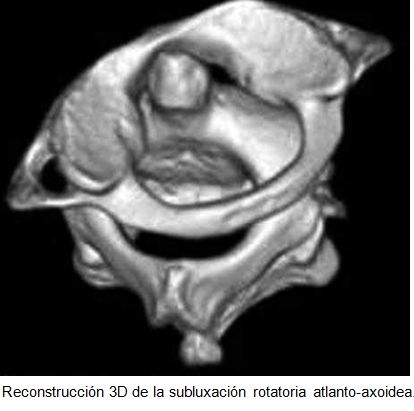

La tortícolis tiene diferentes cualidades dinámicas, dependiendo de si es no paroxística (no dinámico, por ejemplo, muscular congénita y subluxación rotatoria atlantoaxial (C1-C2) o paroxística(dinámico, por ejemplo, paroxístico benigno y espasmódica).

En contraste con tortícolis muscular congénita, en subluxación rotatoria atlanto-occipital, la cabeza se inclina en sentido opuesto del músculo esternocleidomastoideo afectado, con el esternocleidomastoideo acortado, en el lado de la barbilla.

Hay un espasmo muscular en el lado del esternocleidomastoideo “largo”, lo que refleja un intento para corregir la deformidad.

Al examen clínico

Estas dos entidades se pueden separar fácilmente: en pacientes con tortícolis muscular congénita, el ECM del lado contralateral de la rotación de la cabeza se endurece, acorta y hace que la cabeza se incline. En pacientes con subluxación atlantoaxial, el músculo ECM muestra un espasmo  del lado ipsilateral a la barbilla, la que hace girar, lo que sugiere un intento de reducir la deformidad y aliviar el tejido infectado.

En la mayoría de los casos, las anomalías se resuelven en días o semanas con terapia sintomática sola, aunque de vez en cuando la deformidad persiste, lo que resulta en la fijación rotativa.

Los niños con tortícolis puede tener una sub-luxacion  atlantoaxial y la fisioterapia (pueden estar contraindicada.

El diagnóstico temprano y la terapia es esencial en el síndrome de Grisel para prevenir las complicaciones neurológicas, como paraplejia, causada por la dislocación de la apófisis odontoides conduce a la compresión del bulbo raquídeo o un daño de las estructuras neurovasculares adyacentes.

El manejo  de la subluxación rotatoria atlantoaxoideas, va desde medidas conservadoras, a la intervención quirúrgica.

El tratamiento de la tortícolis secundarias a la subluxación atlantoaxoidea,  depende de la gravedad y la duración de la subluxación.

En los casos agudos (menos de 1 semana de duración) y las menos graves, un collar cervical blando, reposo y analgésicos puede ser adecuado. Para los casos más graves, se indica tracción cervical La cirugía puede ser necesaria si tracción no tiene éxito en la reducción de la subluxación.